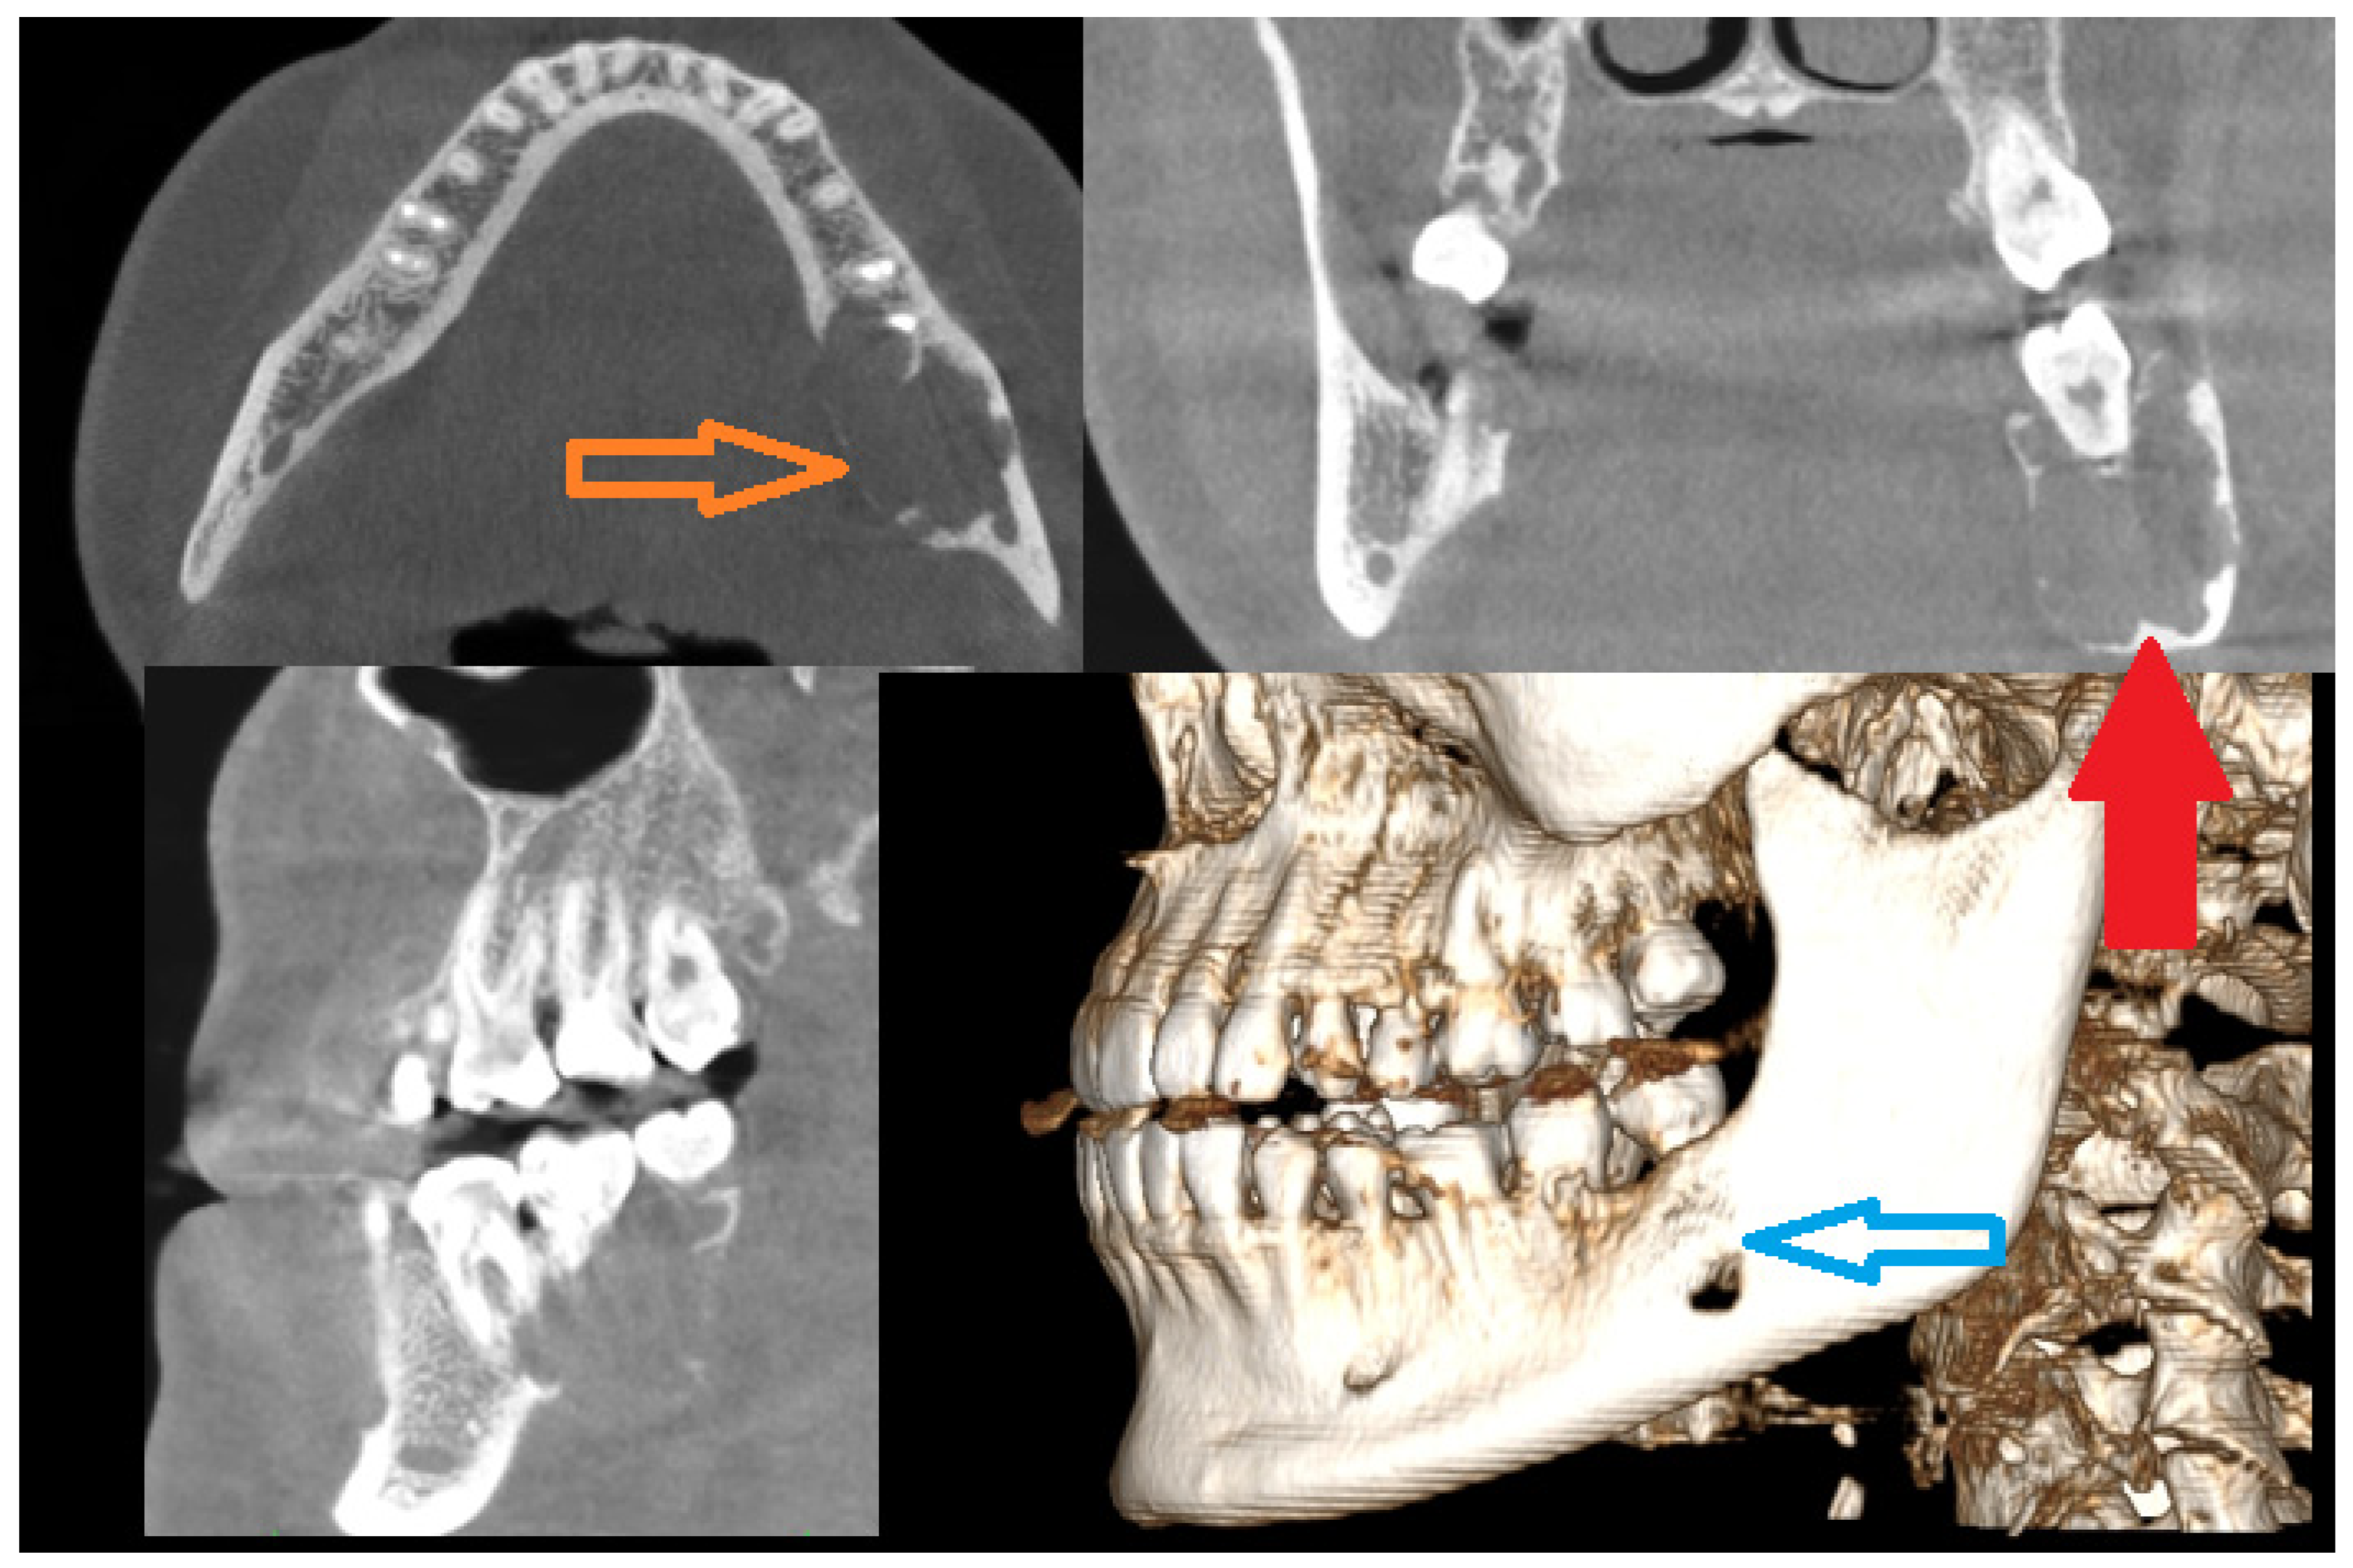

Figure 2. Initial diagnosis excluded any odontogenic cysts and tumors. Endocrine disorders were excluded; however, the value of PTH was in its upper range limits, which was atypical and not conclusive of a BT in PHP. The biopsy and evaluation of calcium–phosphate markers were not significant either. Because of lesion growth, the possibility of pathological fracture, secondary bone disfigurement, and perhaps a necessity in the future for a free-flap, the decision was made to undergo surgery while some of the patient’s own bone was still present. A possible option for a conservative approach was avoided to decrease the risk of any possible pathological mandibular fracture during this bone tumor progression. Because of the possibility of reducing the scope of surgery and maintaining a healthy lower mandibular bone border, it was possible to use an alternative approach different from the typical en-block resection with microsurgical reconstruction. Secondly, because of the patient’s young age and her expectancy for a good and less invasive outcome and avoidance of a facial scar, an intraoral approach was used. Because of the location, a superior-based mandibular body marginectomy with bone ostectomy, teeth removal (36–38), and resection of purple-like gum tumor with prophylactic stable bone osteosynthesis of the mandible was scheduled (two Medartis 2.0 titanium plates with seventeen screws 2.0 7/8 mm, Medartis, Basel, Switzerland). Intraorally, the entire polycystic lesion had a solid appearance without any mineralization or cystic appearance, but in both the radiological and clinical examination, the lesion had an expansile behavior. The lower inferior alveolar nerve was displaced within the tumor’s inferior aspect and was not untacked during surgery. The entire bone defect was filled with allogenic bone grafts (20 cm3 of bone) from the local bio-bank and additional bone marrow aspirate concentrate (BMAC) from the iliac crest, with blood mixed together. Three collagen membranes (Matrix Flex, Athena Marketing, Vadodara, Gujarat, India) were placed on the lingual aspect of the bone and sutured with 4.0 Prolene sutures (Prolene—B.Braun, Melsungen, Germany) to the flaps to ensure more stability to the allogenic bone. Four additional IMF screws (intramaxillary fixation, Medartis, Basel, Switzerland) were applied to avoid any secondary trauma.

Diagnostics 15 02038 g002